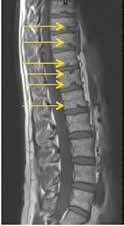

Die erst gegen Ende der Pubertät auftretende Hyperkyphose des Morbus Scheuermann (Abb. 3) entzieht sich durch den Zeitpunkt ihres Auftretens und damit ihrer späten Diagnostik einer effektiven Orthesenbehandlung 10 11 12. Das Potenzial der Orthesenversorgung zur Verhinderung einer Kyphoseprogredienz ist jedoch in Einzelfällen zu nutzen. Besonders Kyphosen im kaudalen Brustwirbelsäulenbereich bieten dabei günstige Hebelverhältnisse.

Die Behandlung von Spondylolyse und Spondylolisthese mittels Orthesen ist aus den Behandlungsempfehlungen weitgehend verschwunden 13 (Abb. 4). Dies ist nur damit erklärbar, dass Orthesen so dargestellt werden, als seien sie zur Ruhigstellung des gesamten Patienten vorgesehen. Das Gegenteil ist jedoch der Fall: Durch eine lokale Stabilisierung und Wirbelsäulenkorrektur wird eine beschwerdearme Aktivierung der Patienten erst wieder möglich.